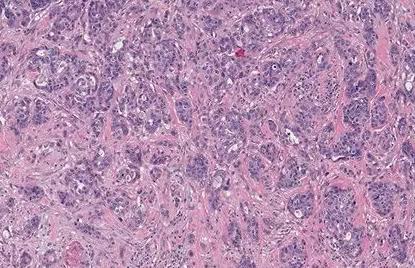

病理示:低分化腺癌。

低分化腺癌,恶性程度高,预后不好